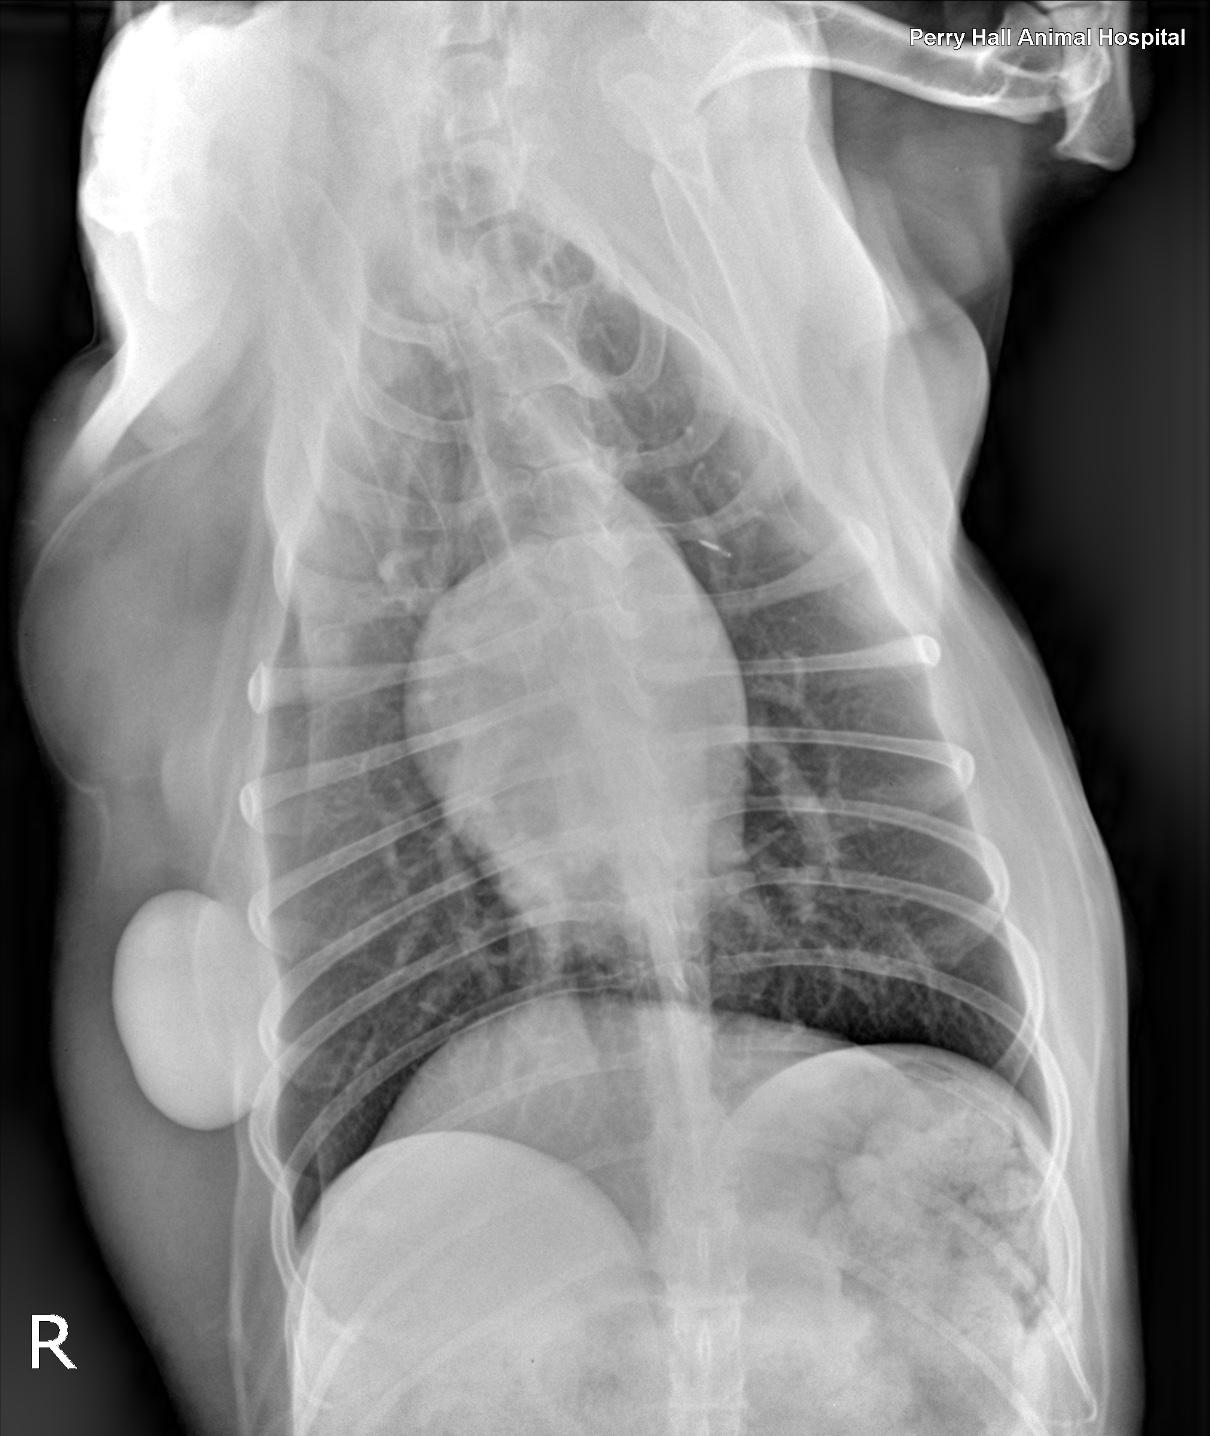

Rads of thorax, right lateral, left lateral and VD: The degree of inspiration was moderate. Osseous structures are within normal limits. Extrathoracic soft tissue structures showed the cervical esophagus was mildly dilated with gas. A subcutaneous, well delineated soft tissue opaque mass lesion measuring 6cm, and a lipoma measuring 10cm were seen along the right lateral chest wall. Intrathoracic structures showed there was an incidental redundant tracheal membrane. The course of the trachea was normal. No mediastinal widening was noted. The cardiac silhouette was small. There was no abnormal prominence of the major vessels. The caudal vena cava was thin. The pulmonary vessels were thin. There was an ovoid, soft tissue, opaque nodule level with the first intercostal space measuring approximately 3cm in diameter. This nodule was visible on both left- and right-lateral views and appeared to be associated with the right cranial lung lobe on the ventro dorsal view. The pulmonary parenchyma showed a mild generalized bronchointerstitial pattern.

The radiographic findings suggest a neoplastic interstitial nodule within the right cranial lung lobe. The location of the nodule is not typical for a primary neoplasia of the lung. Therefore next to a primary neoplasia metastase(s) of another primary tumor have to be considered. There is a lipoma and a subcutaneous soft tissue neoplasia on the right chest wall. The mild bronchointerstitial pattern likely is an age related finding. The potential for current bronchitis is low. The radiographs further show microcardia and under-perfusion of the lung, both of which indicate hypovolemia. There is no radiographic evidence for cardiac disease.